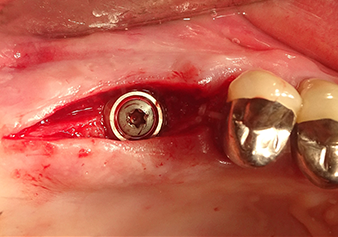

Préparation et augmentation du site implantaire

Après un contrôle intermédiaire (Fig. 4), une étape de préparation ultérieure est exécutée (Fig. 5). Puis on utilise l’insert Z35P hydraulique pour relever la membrane vers la position souhaitée (Fig. 6 et 7). Ensuite, une préparation piézochirurgicale supplémentaire est pratiquée sur le site implantaire, en utilisant pour terminer un burin rotatif et une fraise à épaulement jusqu’à 4,8 mm de diamètre d'implant. Avant l’insertion de l'implant, le matériau d’augmentation (taille de particules env. 0,8-1,6 mm) est introduit sous la membrane de Schneider (Fig. 8).